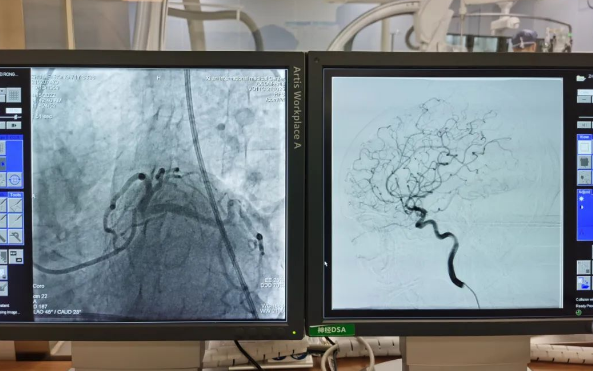

術(shù)前準備就緒后,心內(nèi)二病區(qū)曾廣偉主任、高釗副主任醫(yī)師、神外科陸丹副主任醫(yī)師共同為患者行腦血管造影術(shù) 冠狀造影術(shù)。術(shù)后,朱奶奶恢復良好。

陸丹副主任醫(yī)師介紹,由于腦血管疾病和心血管疾病有著共同的病理變化基礎——動脈粥樣硬化,臨床中,兩類疾病交叉存在的情況十分多見?!靶哪X同治”的模式不僅能讓患者獲得較好治療,還能夠降低患者就醫(yī)的時間成本和經(jīng)濟成本。